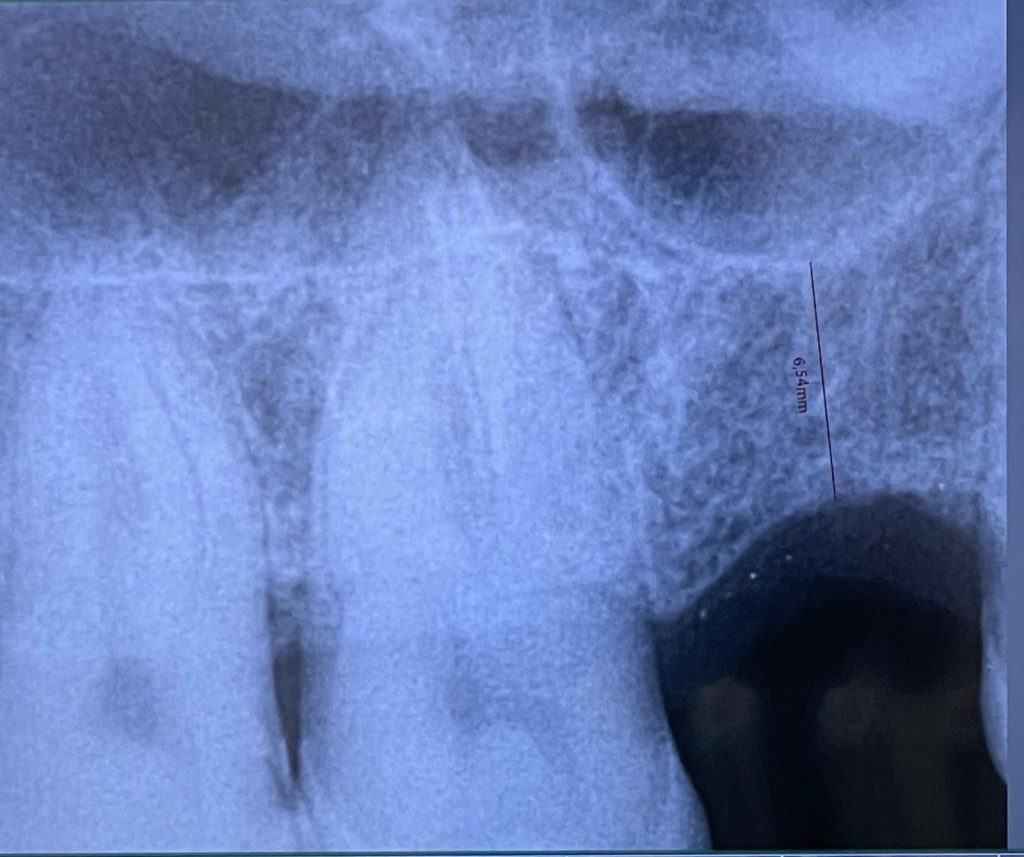

Eccoci con un altro caso del mese in cui vi mostro un intervento dove, data la presenza di una cresta residua insufficiente che non permetteva l’inserimento diretto di un impianto, è stato prima eseguito un mini rialzo di seno mascellare con tecnica MISE ed è possibile notare sopra l’apice dell’impianto un incremento di volume.